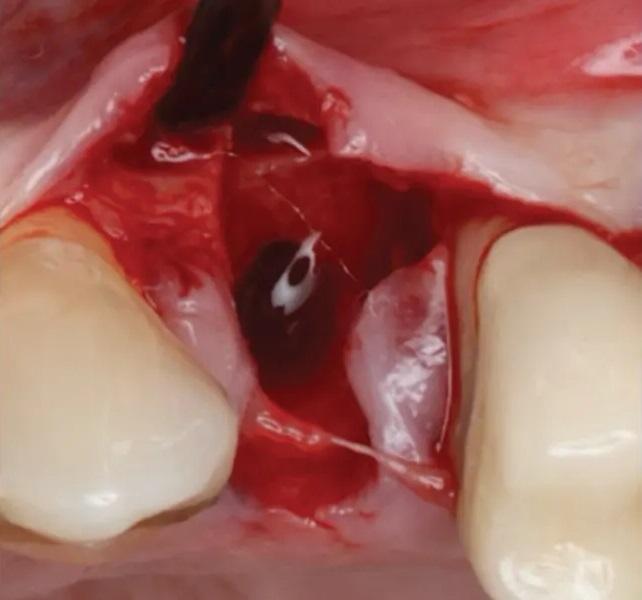

Фото 7. Удаление первого премоляра верхней челюсти слева. Свежая лунка демонстрирует сохраненный контур мягких тканей.

Фото 8. Вестибулярный лоскут слегка отслоен, видны хороший уровень васкуляризации и немедленное образование кровяного сгустка в лунке.